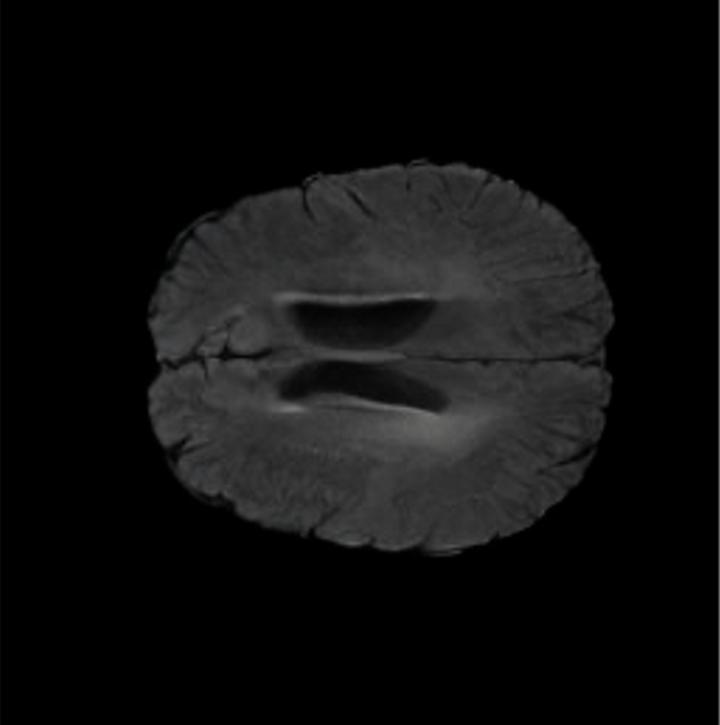

Notably, X-Diffusion achieves sota dB for a few input slices while baselines require more than 60 input slices to achieve similar performance (Figure 7). The margin is more than 12 dB PSNR for the 1-slice input in both the BRATS and the UK Biobank benchmarks (see Table 1 and Figure 6). For reference, two randomly sampled MRIs from the UK Biobank would have a PSNR of 15.95 dB 0.36 (on 4800 randomly sampled examples). The slices from 3D reconstructed volumes at varying depths and axis of rotation visually match the ground truths (see Figures 5 and Figure 4). We also plot the error map (Figure 4) of such X-Diffusion generations to highlight the differences with the ground truth MRIs.

Brain Volumes Preservation. The generated MRIs by our X-Diffusion retain almost the exact same average brain volume vs of the real MRIs.

Tumour Information Preservation. For the brain tumor segmentation, we use a Swin UNETR model[27, 70], trained with random rotation, and intensity as data augmentation. In Figure 5, we highlight the tumor profiles of the generated MRIs compared to the ground truth tumour profile. In the test set with human ground-truth annotations (), the real MRI Dice score is 85.15 while the generated MRIs from a single slice have a dice score of 83.09. This shows how the generated MRIs indeed preserve the tumor information and can act as an affordable and informative pseudo-MRI, before conducting an actual costly MRI examination in hospitals.